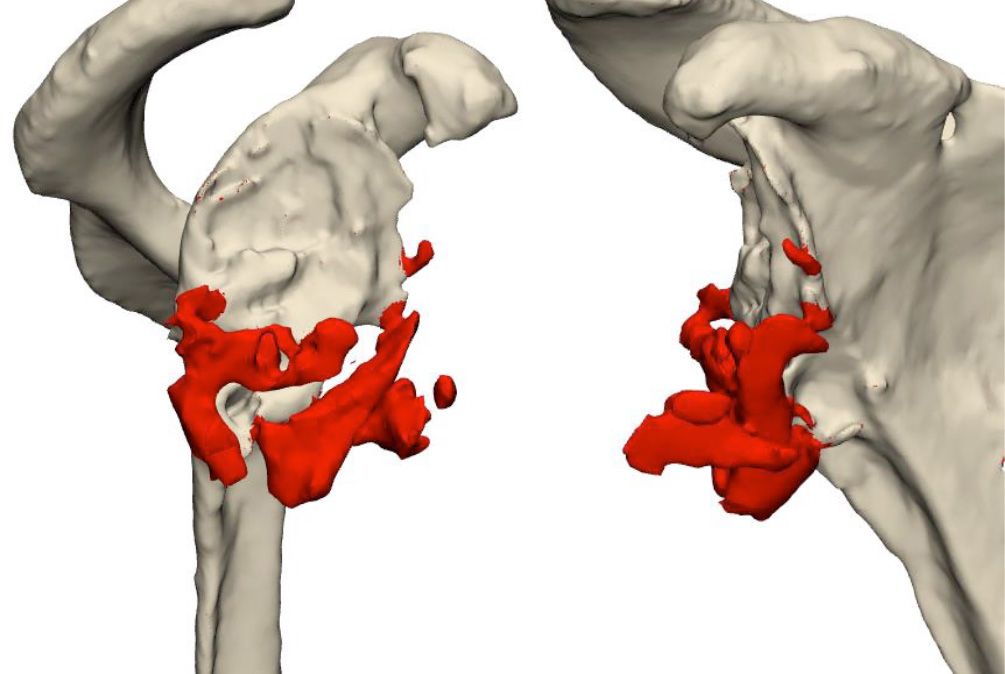

3D CT–Data analysis and resection proposal

- Resection of the inferior bone fragments on the glenoid side

- Cement removal from the humeral cavity

- First design proposal

Design proposal for the glenoid (customLINK)

- customLink glenoid baseplate with TrabecuLink structure

- 15 mm Central peg lenght and 7 cortical screws

- Coracoid and acromial flap

- Excentrical Glenosphere, dia. 42mm, 4 mm ecc.

- Inclination / inferior tilt 5 degree

Design proposal for the humerus (customLINK)

- Modular Revision Stem, 165 mm length, diameter between 18 to 24 mm

- Proximal Body, size M, height +0 mm

- Reverse Humeral Tray, neutral

- Reverse Humeral Insert, UHMWPE, dia. 42 mm, height 3 mm